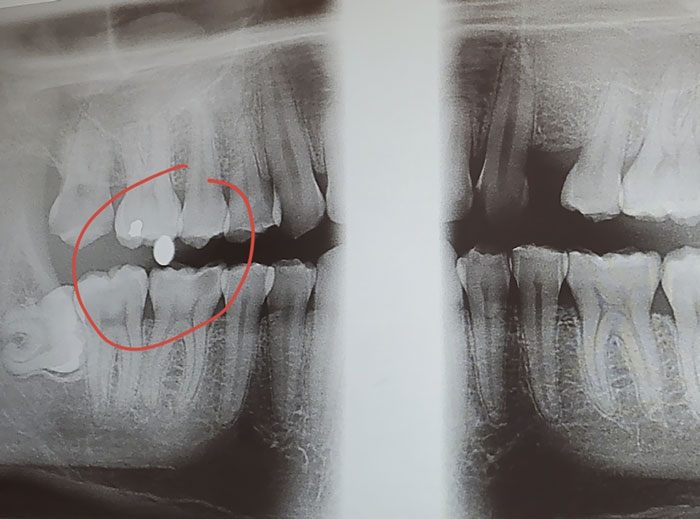

X-Ray From The Dentist Shows A BB From When I Got Shot In The Face About 15 Years Ago